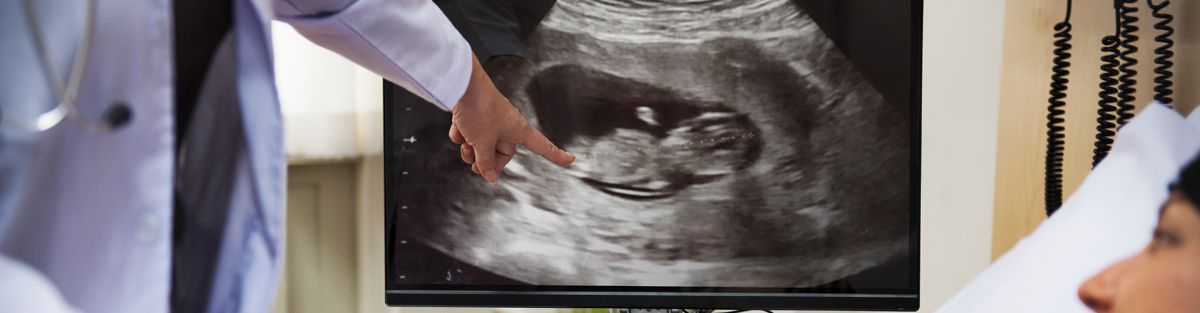

Gebelik süreci, anne adayları için heyecan verici bir dönemdir. Bebeğin sağlığını izlemek ve gelişimini takip etmek amacıyla bir dizi tıbbi test yapılmaktadır. Bu testlerden biri de ultrason muayenesidir. Gebelikte ultrason, anne karnındaki bebeği görmek, gelişimini değerlendirmek ve potansiyel sorunları tespit etmek için yaygın olarak kullanılan bir tıbbi görüntüleme tekniğidir.

Ultrason, yüksek frekansta ses dalgalarını kullanarak iç organları görüntülemek için kullanılan bir tekniktir. Gebelikte ultrason, anne karnındaki bebeği ve çevresindeki yapıları görmek için kullanılır. Bu muayene, genellikle bir jelden oluşan bir madde ile anne karnının üzerine uygulanan bir cihaz yardımıyla yapılır.

Gebelikte ultrason, güvenli ve yaygın olarak kullanılan bir tıbbi görüntüleme yöntemidir. Ancak, her tıbbi müdahale gibi, bu muayene de doktorunuzun önerisi ve gözetimi altında yapılmalıdır. Gebelik sürecinizde düzenli olarak planlanan ultrason muayeneleri, bebeğinizin sağlığını izlemenin ve gelişimini takip etmenin önemli bir parçasıdır.